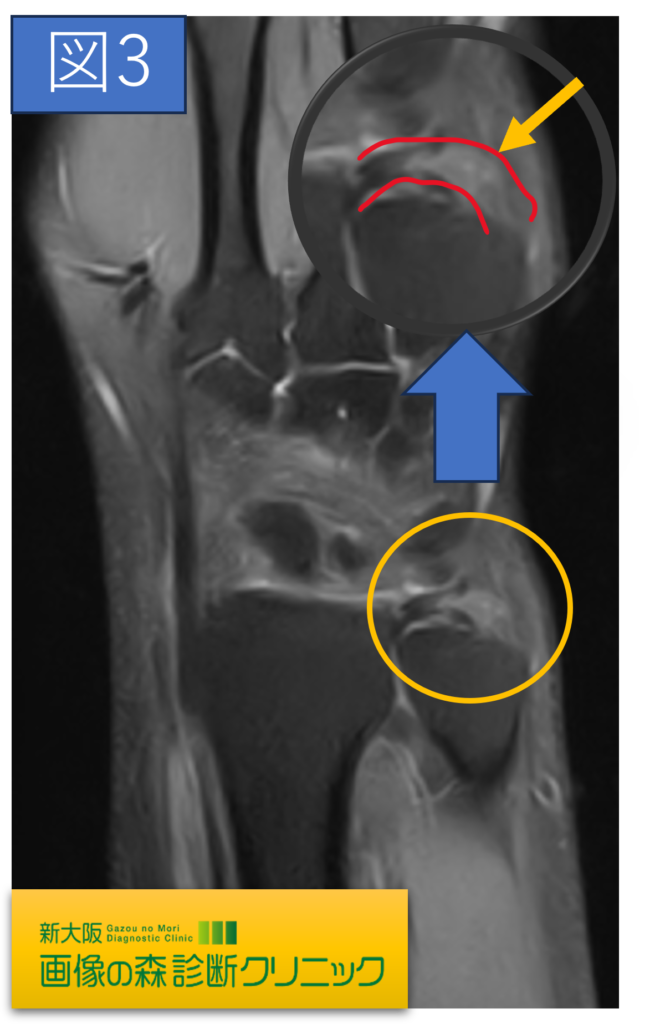

正常MRI画像(冠状断像)

症例画像から図2・図4 〇内にTFCCの損傷を示しています。

正常では靱帯や腱は黒く描出されますが、損傷では、白く高信号に描出されます。